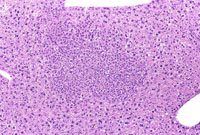

Foci of cellular alteration represent small to large aggregates of tinctorially distinct hepatocytes within the hepatic parenchyma and are sometimes considered putative preneoplastic lesions. They are frequently classified based upon their phenotypic appearance as basophilic, eosinophilic, clear cell, vacuolated, and mixed foci. Occasionally amphophilic foci are identified by the altered arrangement of the hepatic plates without tinctorial distinction from the surrounding hepatic parenchyma. The distinction between a large focus of cellular alteration and a hepatocellular adenoma is often a difficult judgment. A basophilic focus of cellular alteration with irregular boundaries. Basophilic foci are frequently comprised of hepatocytes that are smaller than the surrounding hepatocytes. The tinctorial properties are a function of closely spaced small nuclei and/or increased cytoplasmic basophilia.

Multiple basophilic foci are prominent in this mouse treated with a neonatal dose of diethylnitrosamine.